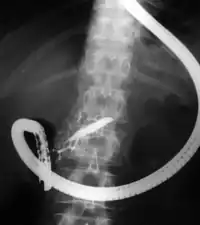

The patient is sedated or anaesthetized. Then a flexible camera (endoscope) is inserted through the mouth, down the esophagus, into the stomach, through the pylorus into the duodenum where the ampulla of Vater (the union of the common bile duct and pancreatic duct) exists. The sphincter of Oddi is a muscular valve that controls the opening to the ampulla. The region can be directly visualized with the endoscopic camera while various procedures are performed. A plastic catheter or cannula is inserted through the ampulla, and radiocontrast is injected into the bile ducts and/or pancreatic duct. Fluoroscopy is used to look for blockages, or other lesions such as stones.[8][9]

When needed, the sphincters of the ampulla and bile ducts can be enlarged by a cut (sphincterotomy) with an electrified wire called a sphincterotome for access into either so that gallstones may be removed or other therapy performed.[10]

Other procedures associated with ERCP include the trawling of the common bile duct with a basket or balloon to remove gallstones and the insertion of a plastic stent to assist the drainage of bile.[11] Also, the pancreatic duct can be cannulated and stents be inserted.